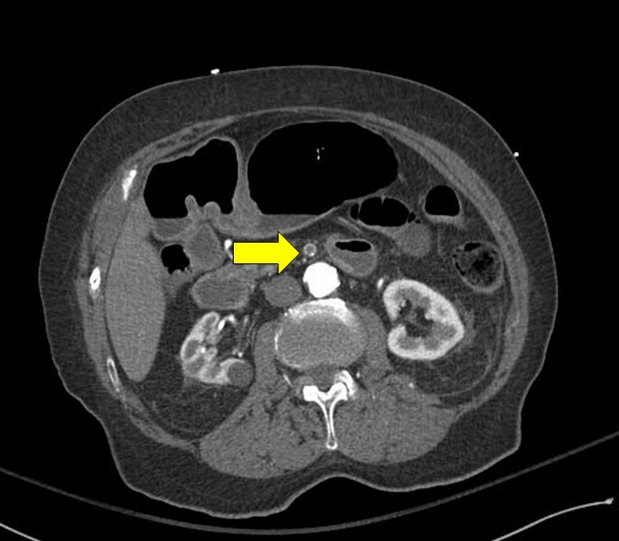

Mesenteric ischemia often presents with vague and nonspecific symptoms and requires a high index of suspicion to avoid delayed diagnosis. The CT angiogram (Figure 4) demonstrates acute thrombosis within the patient’s known superior mesenteric artery stent, with complete obstruction to flow more easily seen on the three-dimensional reconstruction (Figure 5). Emergent exploratory laparotomy is the most appropriate next step to assess bowel viability prior to consideration of revascularization. In this case, extensive small bowel ischemia was present (Figure 6), which progressed to full-thickness necrosis despite successful intraoperative revascularization over the next 24 h. The patient was subsequently transitioned to comfort care.

CT angiogram demonstrating thrombosis within the mesenteric stent.